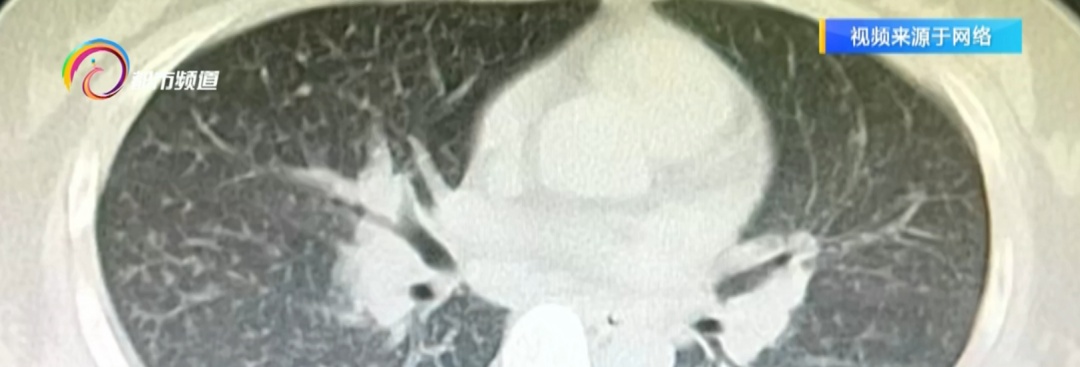

医院确诊为

急性嗜酸性粒细胞肺炎。